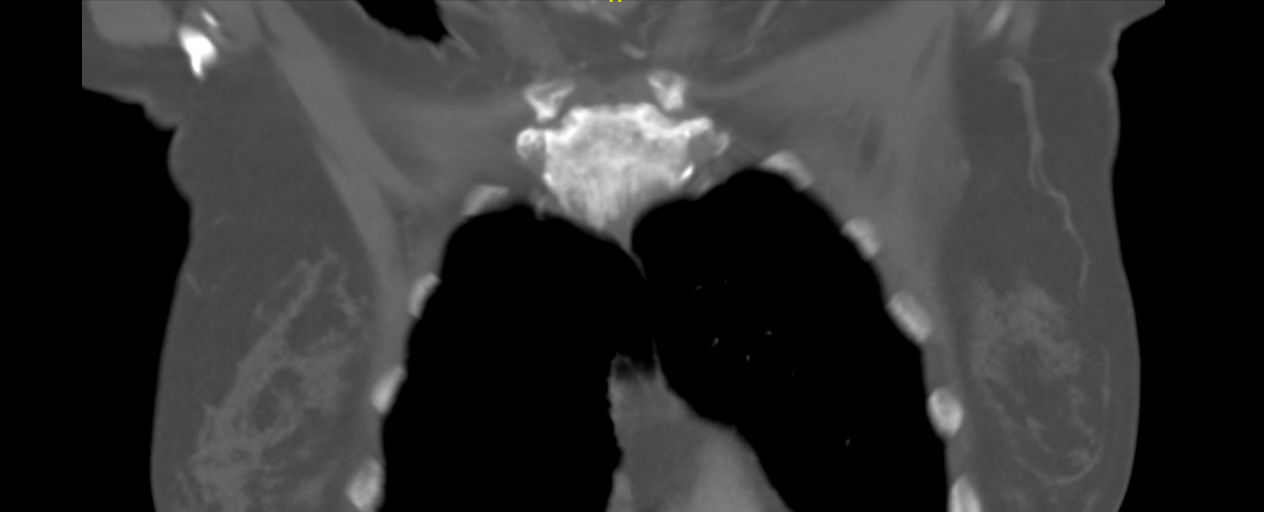

Case Presentation: 57 years old lady with hypertension presented to ER with chest and neck pain for 1 week. Pain was in upper right side of chest and collar bone. Pain character was sharp, 9/10 in intensity, not relieved by acetaminophen, aggravated with movement and without associating factors. On exam, vital signs were normal. She had swelling, erythema and tenderness over manubrium. Laboratory data revealed WBC of 13.7 without bands, C-reactive protein (CRP) of 63 and normal sedimentation rate (ESR). CT scan with contrast was obtained, which revealed osteitis of the manubrium with surrounding soft tissue density, representing inflammation or condition of sclerosis and hyperostosis. MRI showed acute on chronic sterno-manubrial osteomyelitis (OM). Patient was subsequently treated in the hospital with intravenous(IV) Vancomycin and cefepime for OM. Biopsy of manubrium on day 2 of hospitalisation did not reveal findings of acute osteomyelitis. Staining and culture of the sample were negative. Patient was discharged on IV Vancomycin and ceftriaxone for 6 weeks. Despite antibiotics, patient continued to have pain and developed acute kidney injury with supra-therapeutic vancomycin level while taking ibuprofen. She returned to hospital 3 weeks later. Given failure to respond to antibiotics and negative biopsy results, a diagnosis of sternocostoclavicular hyperostosis (SCCH) was made. Bone scintigraphy scan revealed increased uptake throughout manubrium. Antibiotics were stopped, and patient was discharged on prednisone. Outpatient visit 2 weeks later revealed resolution of her symptoms.